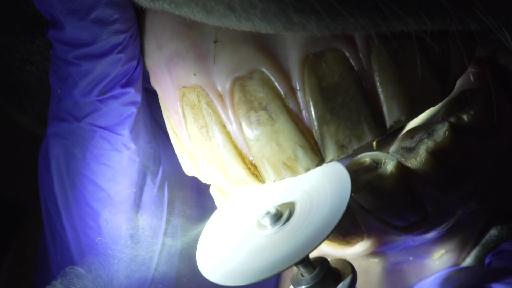

Auch Pferde müssen zum Zahnarzt